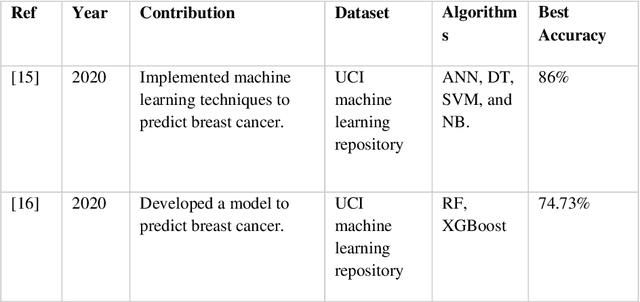

Nowadays, Breast cancer has risen to become one of the most prominent causes of death in recent years. Among all malignancies, this is the most frequent and the major cause of death for women globally. Manually diagnosing this disease requires a good amount of time and expertise. Breast cancer detection is time-consuming, and the spread of the disease can be reduced by developing machine-based breast cancer predictions. In Machine learning, the system can learn from prior instances and find hard-to-detect patterns from noisy or complicated data sets using various statistical, probabilistic, and optimization approaches. This work compares several machine learning algorithm's classification accuracy, precision, sensitivity, and specificity on a newly collected dataset. In this work Decision tree, Random Forest, Logistic Regression, Naive Bayes, and XGBoost, these five machine learning approaches have been implemented to get the best performance on our dataset. This study focuses on finding the best algorithm that can forecast breast cancer with maximum accuracy in terms of its classes. This work evaluated the quality of each algorithm's data classification in terms of efficiency and effectiveness. And also compared with other published work on this domain. After implementing the model, this study achieved the best model accuracy, 94% on Random Forest and XGBoost.